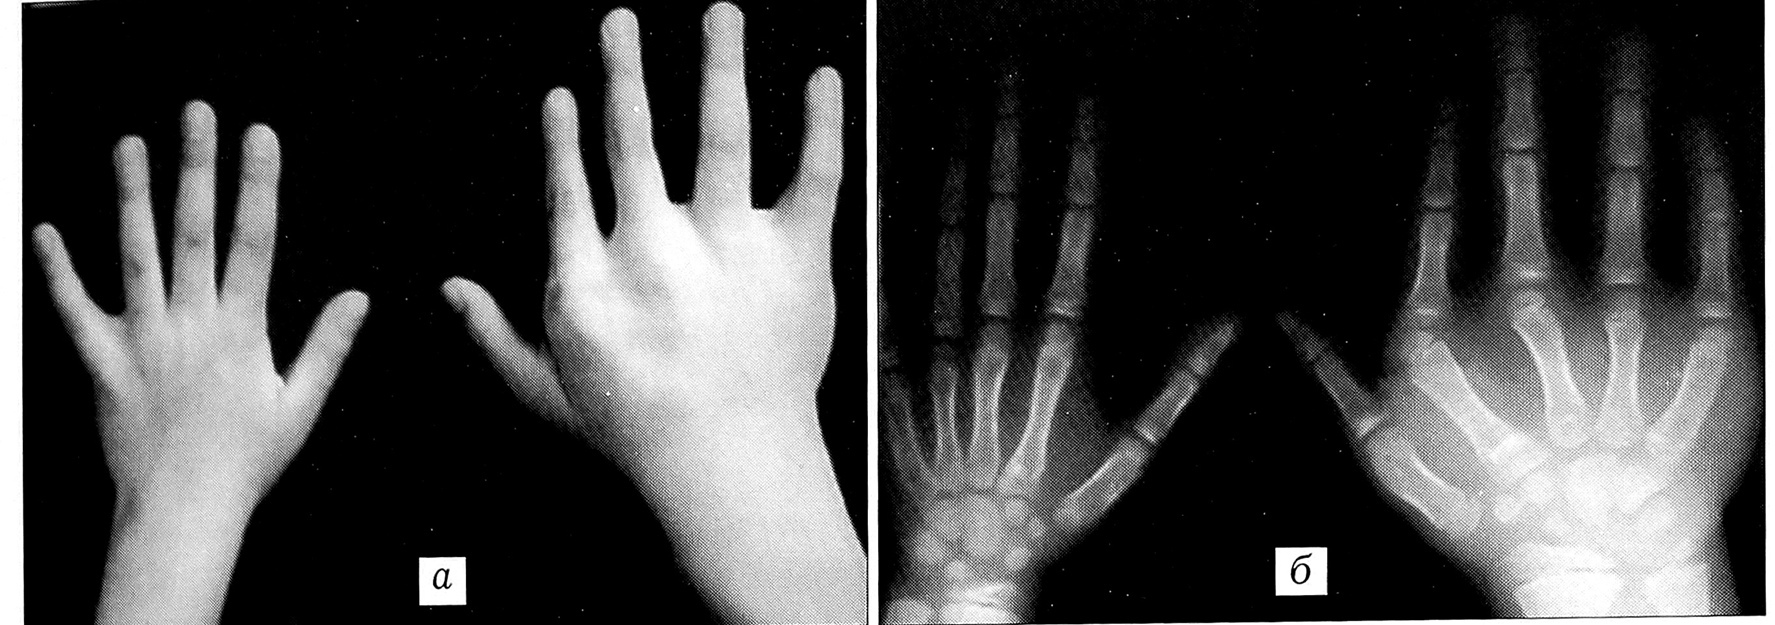

1-я форма. Пораженный сегмент увеличен преимущественно за счет мягких тканей. Костная часть увеличена в меньшей степени как по длине, так и по объему. Увеличение мягких тканей локализуется в основном на ладонной поверхности и в области тенара, уродует форму сегмента и приводит к резкому ограничению сгибания в пястно-фаланговых, межфаланговых суставах, переразгибанию в них, ухудшению функции схвата (рис. 1);

2-я форма. Пораженный сегмент конечности увеличен пропорционально, в большей степени за счет костной части. Имеется ограничение сгибания в межфаланговых суставах, часто присутствует клинодактилия в межфаланговых, пястно-фаланговых суставах в ульнарную или радиальную сторону (рис. 2);

Рис. 1. Внешний вид (а) и рентгенограмма (б) кистей больной К. 11 лет с врожденным гигантизмом III пальца правой кисти, 1-я форма.

Рис. 2. Внешний вид (а) и рентгенограмма (б) кистей больной С. 7 лет с врожденным гигантизмом III и IV пальцев правой и IV пальца левой кисти, 2-я форма.